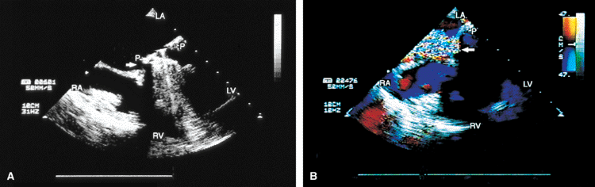

FIGURE 5.28. St. Jude aortic prosthesis: normal. A. Prosthetic aortic valve (PAV) leaflets (arrowhead) and suture ring (arrow), imaged in short axis. B. R marks the suture ring, also imaged in short axis but without the leaflets. C,D. M-mode tracings demonstrate normal motion of the prosthesis aortic valve (AV). E. An arc-like prosthetic side lobe artifact (R). G is the intraluminal tube graft in the aorta (AO). DIAS, diastole; LA, left atrium; RA, right atrium; PA, pulmonary artery; RVO, right ventricular outflow tract; RV, right ventricle; SYS, systole. |